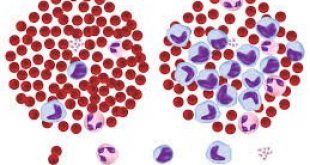

Ο ιός της ηπατίτιδας C είναι από τους κυριότερους παράγοντες της χρόνιας ηπατικής νόσου. Αποτελεί περίπου το 15% της οξείας ηπατίτιδας, το 70% της χρόνιας ηπατίτιδας και το 50% της κίρρωσης του ήπατος, της ηπατικής ανεπάρκειας και του καρκίνου του ήπατος. Η χρόνια ηπατίτιδα C ποικίλει όσο αφορά την πορεία και την συμπεριφορά της. Στην μία μεριά είναι ασθενείς χωρίς συμπτώματα και ευρήματα και με φυσιολογικές τρανσαμινάσες.

Η βιοψία του ήπατος δείχνει βέβαια ότι υπάρχει χρόνια φλεγμονή αλλά αυτή είναι ήπια και με καλή πρόγνωση. Στην άλλη μεριά είναι ασθενείς με σοβαρή ηπατίτιδα C που έχουν συμπτώματα , HCV-RNA στο αίμα, αυξημένες τρανασαμινάσες και οι οποίοι τελικά θα αναπτύξουν κίρρωση και ηπατική ανεπάρκεια. Ανάμεσα στα δύο αυτά άκρα είναι πολλοί ασθενείς με ήπια ή καθόλου συμπτώματα , ήπια ή μέτρια αύξηση των τρανσαμινασών και με αβέβαιη πρόγνωση. Η χρόνια ηπατίτιδα C κάνει κίρρωση , ηπατική ανεπάρκεια και καρκίνο του ήπατος. Η έρευνα έχει δείξει ότι ένα 20% των ασθενών με χρόνια ηπατίτιδα C θα κάνουν κίρρωση ήπατος μέσα σε 10-20 έτη ένα πολύ μικρό ποσοστό θα κάμει καρκίνο. Ο ιός της ηπατίτιδας C ευθύνεται για τις μισές περίπου περιπτώσεις πρωτοπαθούς ηπατοκυτταρικού καρκίνου στον αναπτυγμένο κόσμο. Οι άντρες , οι αλκοολικοί, οι ασθενείς με κίρρωση, ηλικία μεγαλύτερη από τα 40 , αυτοί που έχουν πάθει την λοίμωξη ανάμεσα στα 20 και τα 40 έχουν μεγαλύτερη πιθανότητα να αναπτύξουν καρκίνο από χρόνια ηπατική νόσο λόγω της ηπατίτιδας C.